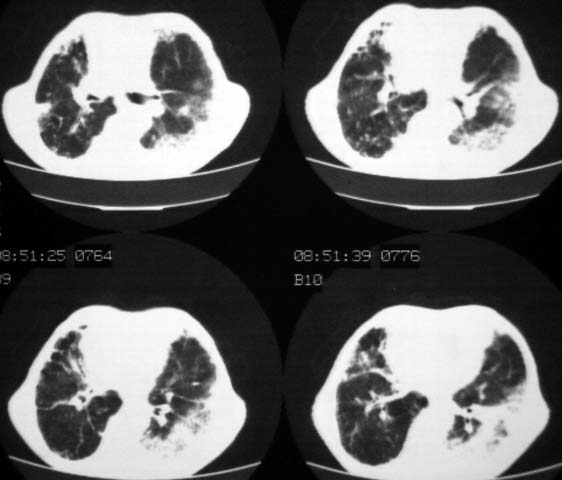

男,85岁,发热2月, 血常规:hgb99g/l.rbc2.55×1012/l.wbc3.8×109/l.n78.2%  l20.7% m1.1%.  hct26.3% .血沉20mm/hg.痰检结核杆菌阴性。ddp阳性。痰少粘稠色白。无咳血。

1.右上肺陈旧性肺结核灶;

2.左上肺、双下肺及右中叶肺炎(左上肺肺炎治疗后好转)

右上肺陈旧性肺结核灶,双肺感染灶〔大部份纤维化〕,肺气肿.

双肺继发型结核

双肺继发型肺结核,肺纤维化,肺气肿,胸膜肥厚黏连。